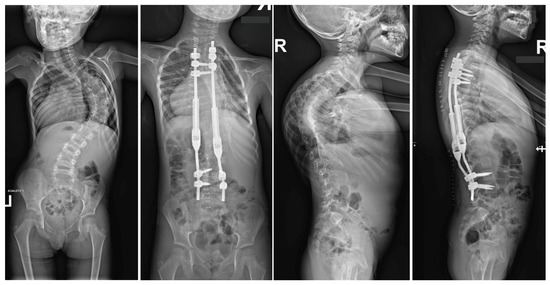

Large spinal deformities, especially those originating from underlying neuro-muscular conditions or severe lumbar scoliosis, can pose a significant challenge when it comes to dealing with pelvic obliquity [62,63]. The presence of pelvic obliquity can lead to incorrect sitting posture and persistent pressure ulcers, making it a crucial issue to address for achieving a positive outcome; nevertheless, it is a task that is often intricate and multifaceted [63]. In the realm of addressing pelvic obliquity, intraoperative halo traction (HT) emerges as a valuable adjunct for improving the correction of this condition. A research study involving a cohort of 40 patients with neuromuscular scoliosis who underwent posterior spinal fusion with an extension of fixation to the pelvis highlighted that 20 of these patients were subjected to intraoperative HT [62]. The initiation of HT took place subsequent to the induction of anesthesia, with each halo being firmly secured by four pins. Following this, a sturdy Kirschner wire was carefully inserted through the distal femur on the side exhibiting the elevated hemipelvis. Upon assuming the prone position in the conventional manner, a traction of 6.8 kg was applied to the halo, which was then gradually escalated to an average of 11.3 kg until the pelvis achieved the desired alignment. The outcomes of this intervention indicated a notable 78% correction in pelvic obliquity within the HT group, in contrast to 52% in the control group [62]. Similarly, a detailed case report by Huang et al. illustrated the successful rectification of severe pelvic obliquity through the implementation of intraoperative HFT [63]. A separate study by Hamzaoglu et al. delved into the cases of 15 patients with thoracic scoliosis who underwent a treatment regimen involving intraoperative HFT in conjunction with posterior-only instrumentation [58]. Unlike prior analyses, HFT was not specifically employed for addressing pelvic obliquity in this scenario. The established protocol entailed obtaining a pre-operative traction radiograph while the patient was under anesthesia, resulting in an average enhancement of 51% in the major thoracic curve. In instances where the curve did not exhibit adequate correction, extensive facet resection and posterior release procedures were carried out. Noteworthy investigations focusing on intraoperative HFT have not documented any complications linked to traction [59]. Owing to the transient nature of the traction utilized, issues commonly associated with pre-operative traction, such as infections at the pin sites or loosening, are anticipated to be less prevalent in occurrence. Barsoum et al. chronicled a case involving an adult patient who was subjected to 2.3 kg of traction using Gardner-Wells tongs, and subsequently experienced a post-operative cranial nerve VI palsy [61]. However, reassuringly, this neurological impairment was completely resolved during the 6-month follow-up evaluation. Figure 4 shows X-rays of a 14-year-old girl treated with intraoperative halo-femoral traction.

Figure 4.

Radiographs taken before and after surgery at the last follow-up appointment depicting a 14-year-old female with severe adolescent idiopathic scoliosis who underwent intraoperative halo-femoral traction, followed by multi-level Ponte osteotomy and posterior spinal fusion in a single-stage surgical procedure.